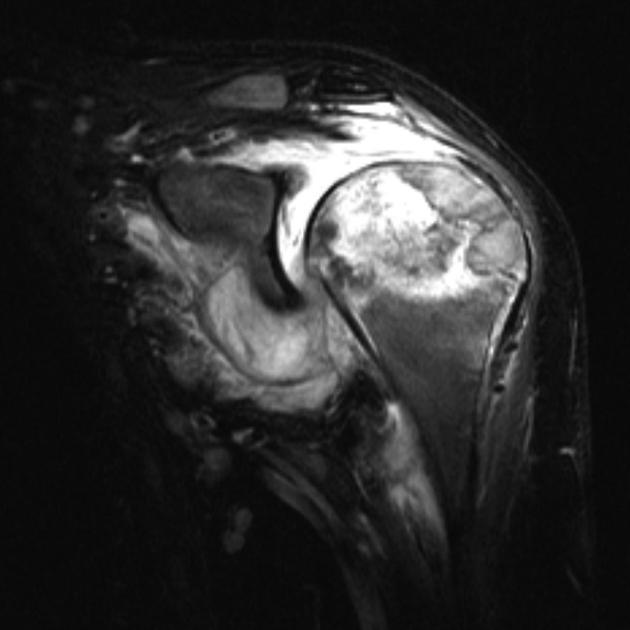

Diagnosis?

MRI findings?

Chondroblastoma. Benign cartilaginous neoplasm common in the 2nd-3rd decades of life.

Circumscribed osteolytic leseion in the epiphysis with a sclerotic rim. Can have calcified chondroid matrix (30-50%). MRI: signal typical of cartilage- low to intermediate T1, intermediate to high T2. Surrounding edema common.